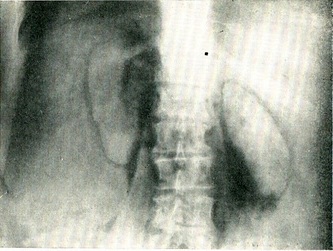

Розрізняють два основних типи ниркової миски. Перший тип - ампулообразная балія порівняно великих розмірів із трьома короткими і широкими чашечками - верхній, середній і нижній; балія розташована поза ниркової паренхіми, медіально від неї; ємність її дорівнює приблизно 8-10 мл При другому, ветвистом, тип балії її розміри невеликі, чашечки довгі, вузькі; балія розташована всередині ниркової паренхіми (рис. 38); ємність її не перевищує 3-4 мл

Рис. 38. Позанирковий (праворуч) і внутрипочечный (ліворуч) тип ниркової миски. Ретроградна пієлограма.